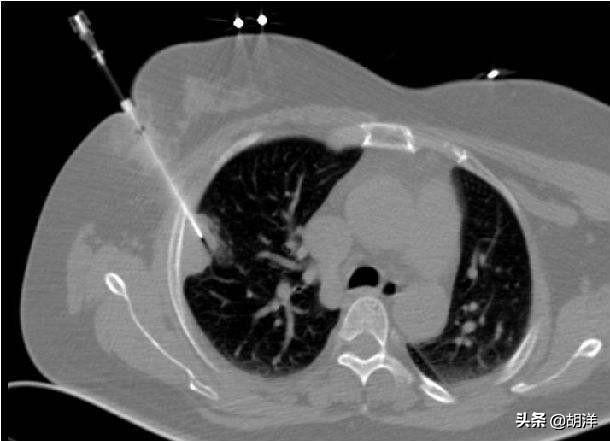

肺穿刺和淋巴结穿刺都是同样的原理,这些检查都必须要在一定的设备的辅助之下进行,比如说在CT定位下或者是彩超定位下,找到目标病灶,确定进针的位点,用活检枪或者是普通的细针扎入病灶进行抽吸,抽吸出来的细胞或者是组织标本进行检查,如果找到游离的或者固定在组织当中的结核菌的话也可以确诊。